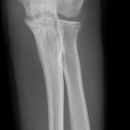

Ellenbogenluxation